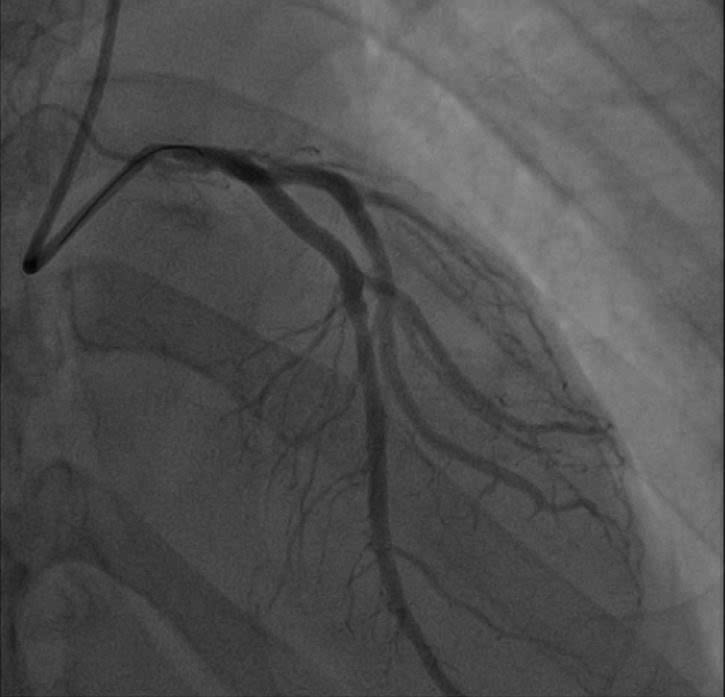

Các bác sĩ Bệnh viện E vừa cấp cứu vừa hồi sức và khẩn trương thực hiện các thăm dò cận lâm sàng tìm nguyên nhân cho người bệnh. Kết quả chụp động mạch vành đã hé lộ nguyên nhân thực sự: Động mạch liên thất trước (LAD) – nhánh động mạch quan trọng nhất nuôi tim – đã bị tắc nghẽn tới 99%. Đây là hậu quả của tình trạng xơ vữa lan tỏa, dù trước đó anh M. chỉ có biểu hiện đau thắt ngực nhẹ mà anh lầm tưởng là trào ngược dạ dày.

Các bác sĩ thực hiện can thiệp mạch vành qua da (PCI) cho người bệnh. Kết quả chụp mạch số hóa xóa nền (DSA) xác định tổn thương hẹp khít 99% đoạn gần nhánh liên thất trước (LAD) – vốn được mệnh danh là "động mạch của sự sống". Các bác sĩ tim mạch can thiệp đã nhanh chóng triển khai kỹ thuật đặt Stent, giải phóng điểm tắc nghẽn, tái lập dòng chảy mạch vành để cứu vãn vùng cơ tim đang thiếu máu cục bộ cấp tính và ngăn chặn các cơn loạn nhịp nguy hiểm.